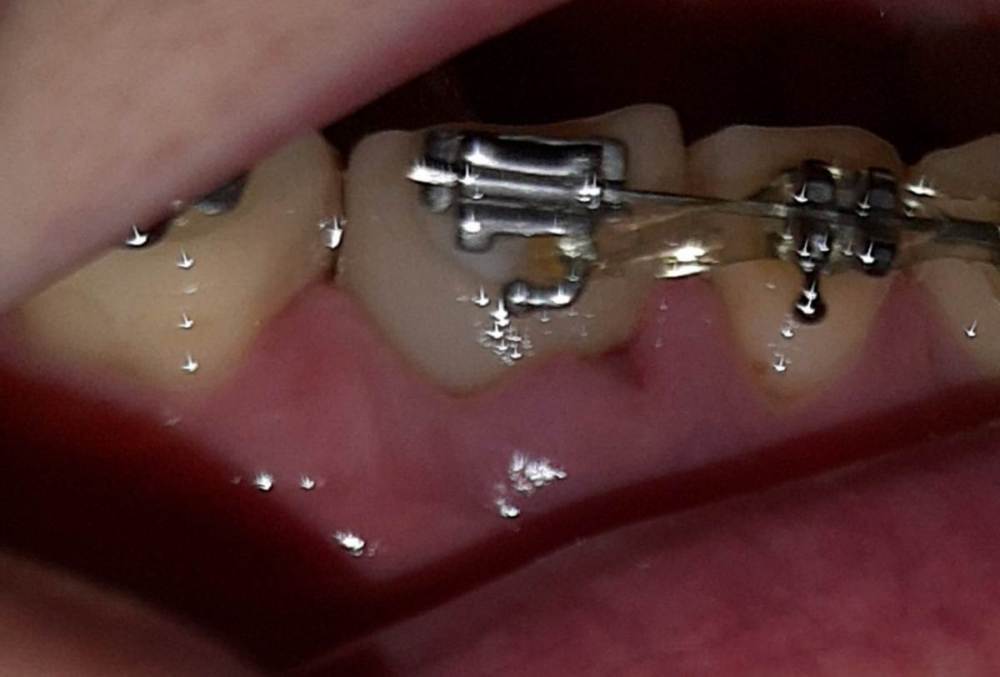

Выход костного материала через 1 год и 3 месяца после наращивания костной ткани

Здравствуйте, возможен ли выход костного материала наружу  через 1 год и 3 месяца после имплантации? Если возможен, то в чем причина? И второй вопрос  - где должна быть коронка, где красные линии, или где желтые, и что это на снимке - отмечено зеленым?